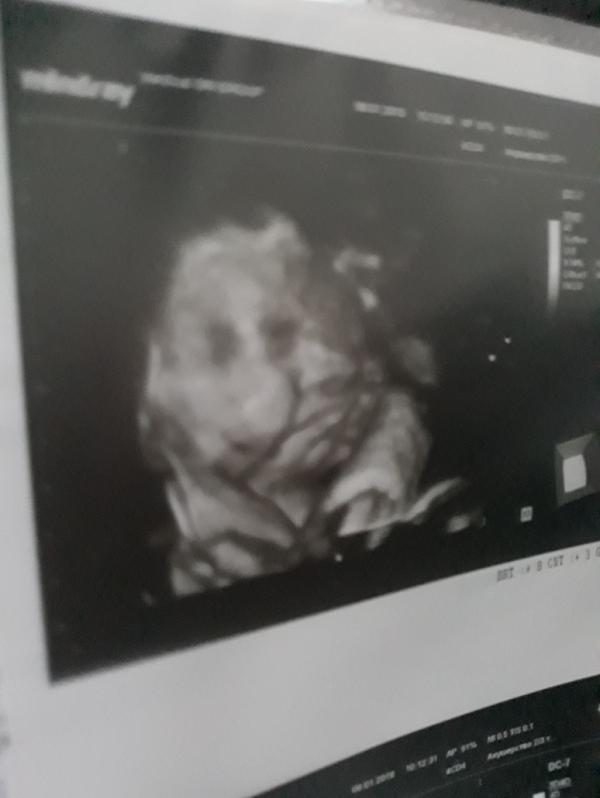

Сходили сегодня на 3д узи, никак наша девчушка не хочет показываться(( и руками закрывалась, отворачивалась. Единственное что удалось рассмотреть это пухлые щечки и недовольное выражение лица😂 УЗИст сказал на папу похожа😂